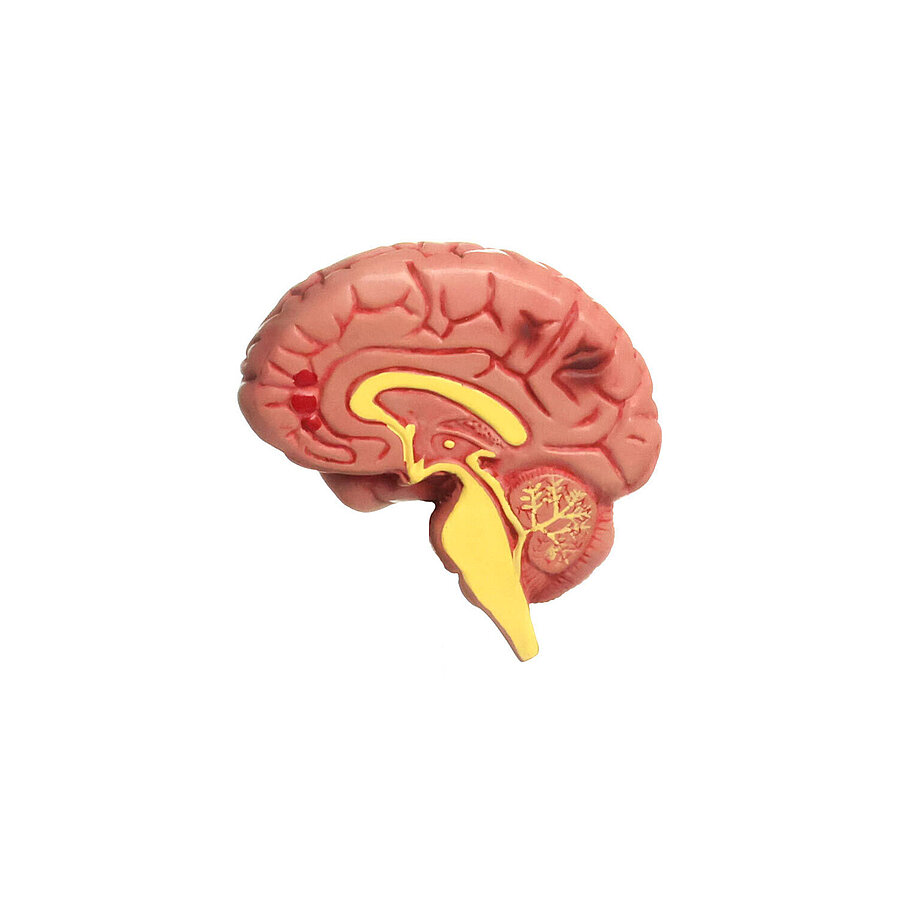

Modell der Hypertonie-Folgen

Zeigt die Folgeerkrankungen des Bluthochdrucks

Anatomische Strukturen sind aufwändig koloriert

Einzelne Organe bei Bedarf abnehmbar